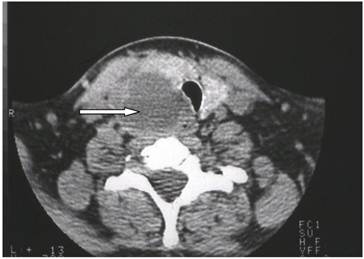

Tomography Density measurements can assist in differentiating abnormal parathyroid tissues from lymph nodes and normal thyroid tissue 19.

However, the only feature that may permit the preoperative diagnosis of parathyroid cancer is clear evidence of invasion into adjacent tissue. Tomography was performed in one patient and demonstrated a cystic mass at the inferior aspect of the thyroid lobe (Fig 1).

Enhanced neck computed tomography showing a cystic mass (arrow) at the inferior aspect of the right thyroid lobe with a tracheal compression.

Differential diagnosis includes thyroid carcinoma and benign parathyroid disease 19.